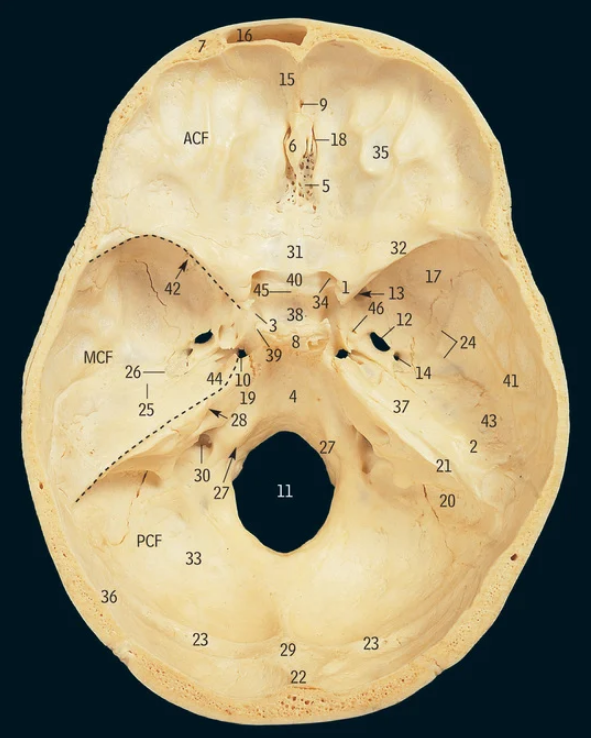

5

Cribiform plate

6

Crista galli

17

Greater wing of sphenoid bone

32

Lesser wing of sphenoid bone

38

Pituitary fossa

34

Optic canal

42

Superior orbital fissure

12

Foramen ovale

13

Foramen rotundum

14

Foramen spinosum

27

Hypoglossal canal

11

Foramen magnum